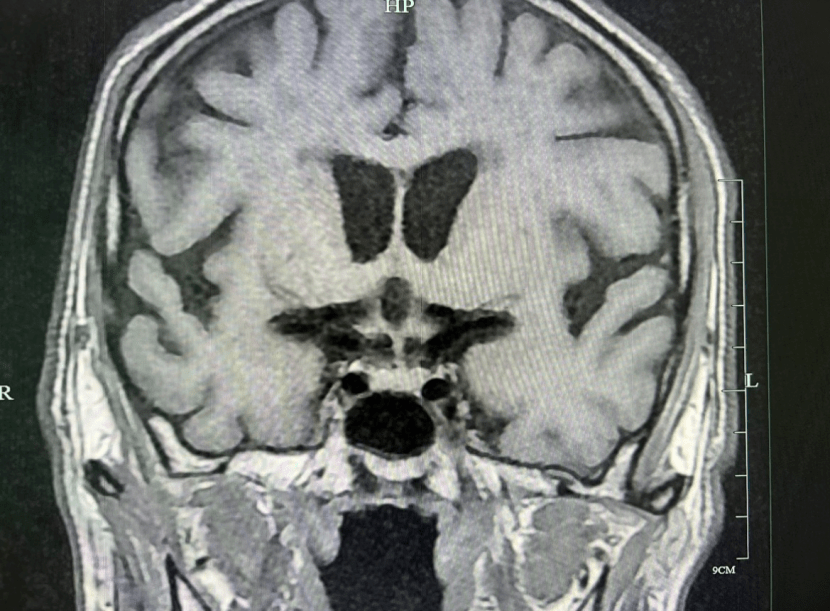

血浆皮质醇:0.99ug/dl,促肾上腺皮质激素:<1.00pg/ml,甲功:游离三碘甲状原氨酸:1.49pmol/L,游离甲状腺素:1.53pmol/L,促甲状腺激素:>100.00uIU/ml,抗甲状腺过氧化物酶抗体:28.97IU/ml,抗甲状腺球蛋白抗体:16.28IU/mL,促甲状腺素受体抗体:<0.80Iu/L;性腺六项:促黄体激素:3.43mIU/ml,促卵泡激素:8.12mIU/mL,睾酮:3.62ng/ml,生长激素:2.82ng/ml;胰岛素样生长因子1.15ng/ml;空腹血糖:3.98mmol/L;空腹胰岛素测定:2.720pmol/L,空腹C肽测定:0.180nmol/L;电解质:钠127.00mmol/L。垂体MRI显示垂体柄增粗。

结合患者临床症状、体征及实验室、影像学检查,祁燕主任医师考虑为垂体免疫相关不良反应(垂体炎垂体前叶功能减退症),遂予口服氢化可的松:8am:20mg,4pm:10mg。